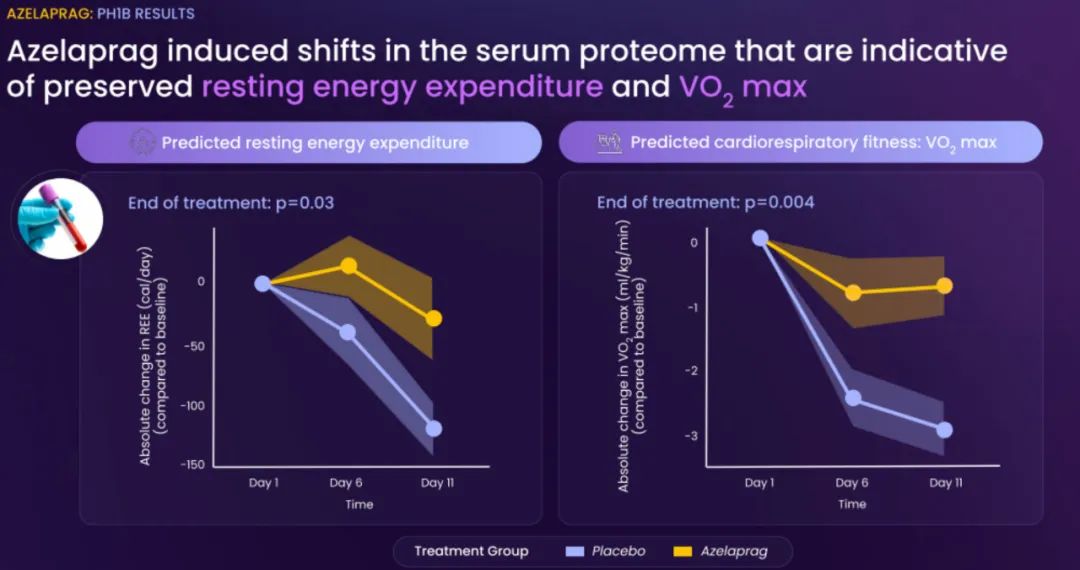

BioAge Labs的主要关注点是代谢疾病,这是全球最大的医疗保健挑战之一。BioAge Labs的主要候选产品 Azelaprag是一种口服小分子,在8个 1 期临床试验中,265 名受试者的耐受性良好。在临床前肥胖模型中,azelaprag 显示出能够使胰高血糖素样肽-1 受体 (GLP-1R) 激动剂诱导的体重减轻增加一倍以上,同时恢复健康的身体成分并改善肌肉功能。

这些临床前结果得到BioAge Labs在卧床老年人中进行的 1b 期临床试验的支持,在该试验中,BioAge Labs观察到在 10 天内接受 azelaprag 治疗的受试者的肌肉萎缩减少、肌肉质量保持良好并且新陈代谢得到改善。